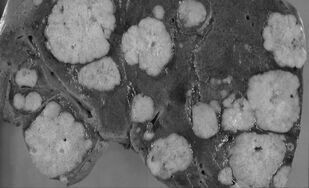

Опухоли гепатопанкреатодуоденальной зоны

Учебное пособие посвящено хирургическим опухолям гепатопанкреатодуоденальной зоны. Освещены вопросы анатомии, физиологии гепатопанкреатодуоденальной зоны, классификация опухолей, методы диагностики и лечения, возможные послеоперационные осложнения.